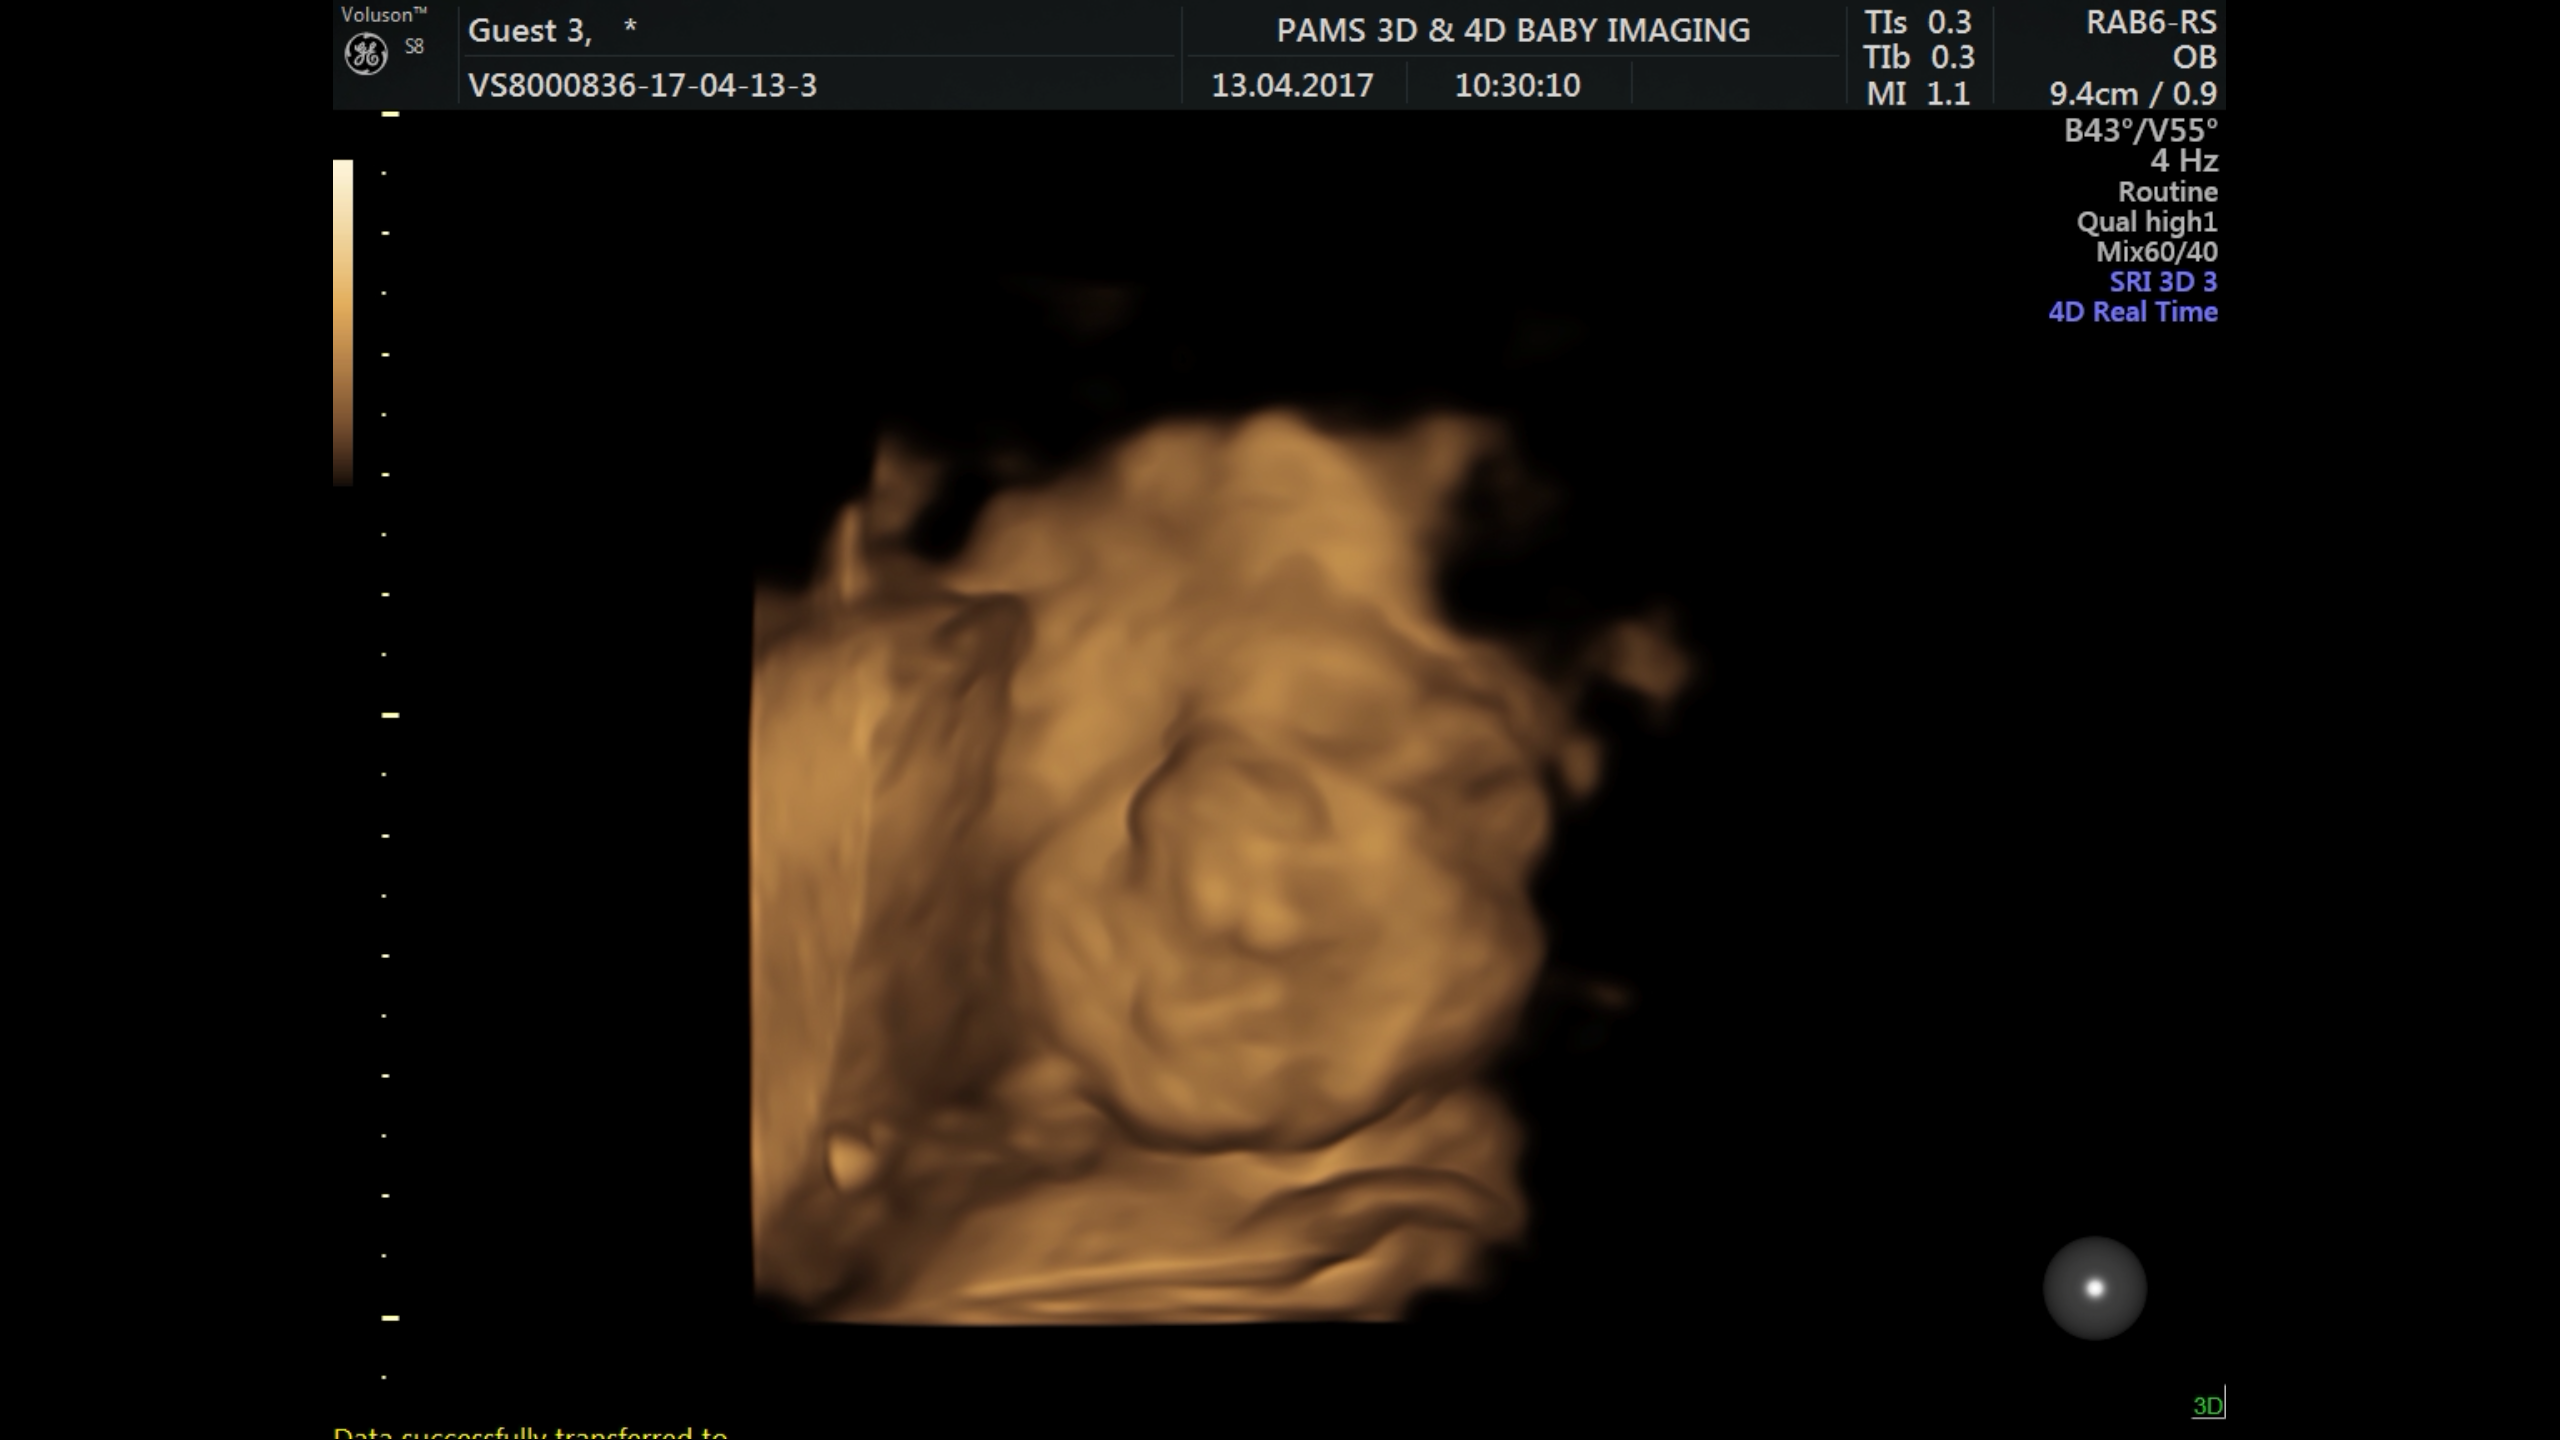

Screenshot_20170413-130313 Share this:Tweet Email a link to a friend (Opens in new window) Email Like Loading...